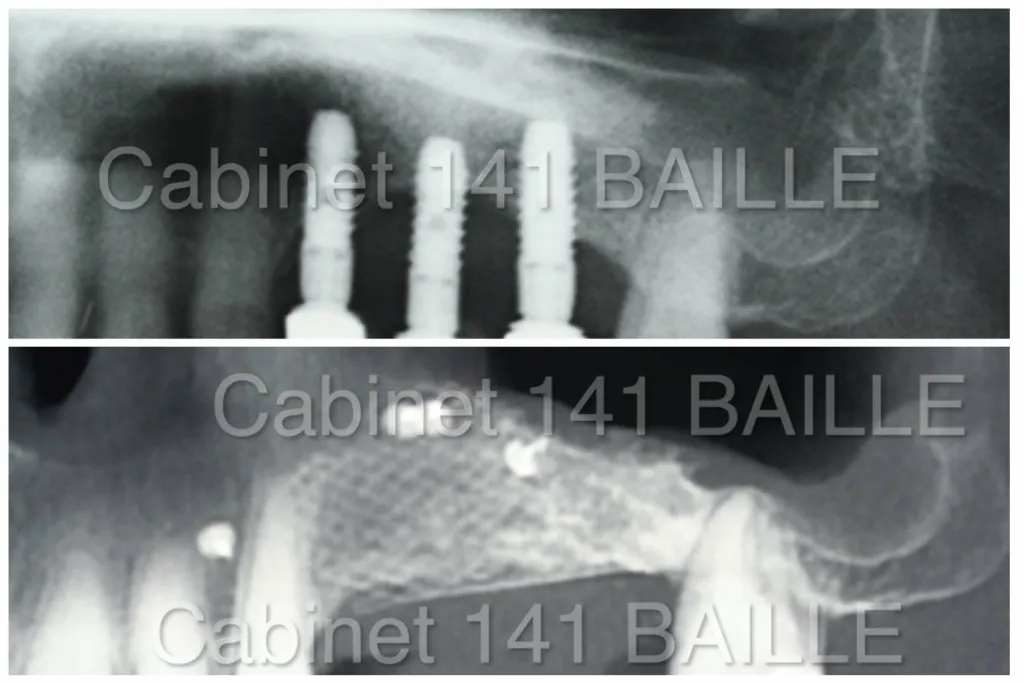

La R.O.G nous permet de traiter les cas complexes d'implantologie caractérisés par un manque d'os au niveau des maxillaires.Les greffes d'os et régénérations osseuse guidée nous permettent de réaliser des augmentations du volume d'os avant la mise en place des implants dentaires.

La régénération osseuse guidée permet de faire des augmentations de volume osseux avant de mettre en place des implants dentaires en greffant de l'os sur le maxillaire.Explications du Dr Tourrolier Didier.

Préalablement à la pose d'implant , il est souvent nécessaire de greffer de l'os sous le sinus afin de pouvoir placer des implants.Explications.